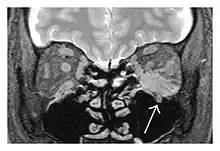

Infraorbital nerve enlargement (IONE) is considered to be a particularly suspicious sign of IgG4-ROD, but seems to occur only when inflammation is in direct contact with the infraorbital canal.[10] IONE is defined as the infraorbital nerve diameter being greater than the optic nerve diameter in the coronal plane.

![]() Enlargements in the left inferior rectus muscle and infraorbital nerve (arrow) in a 65-year-old man with a serum IgG4 of 404 mg/dL.[1] (T2-weighted MRI) |